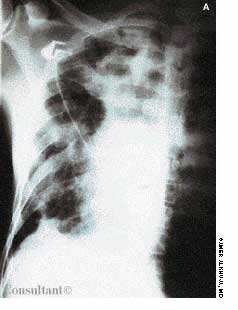

Police brought a delirious, combative 24-year-old man to the emergency department. The patient was unable to provide any history on arrival, but his scarred, blistering lips and his vital signs (blood pressure, 166/102 mm Hg; heart rate, 97 beats per minute; respiratory rate, 24 breaths per minute; and temperature, 38.2°C, or 100.9°F) led to a possible diagnosis of cocaine-induced delirium.